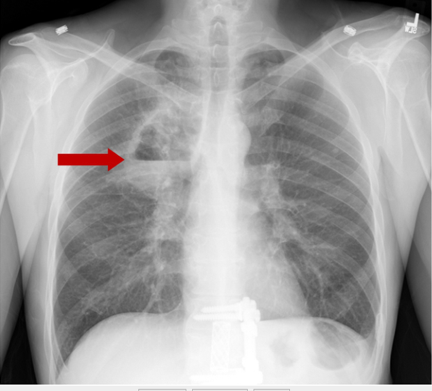

Lung Abscess